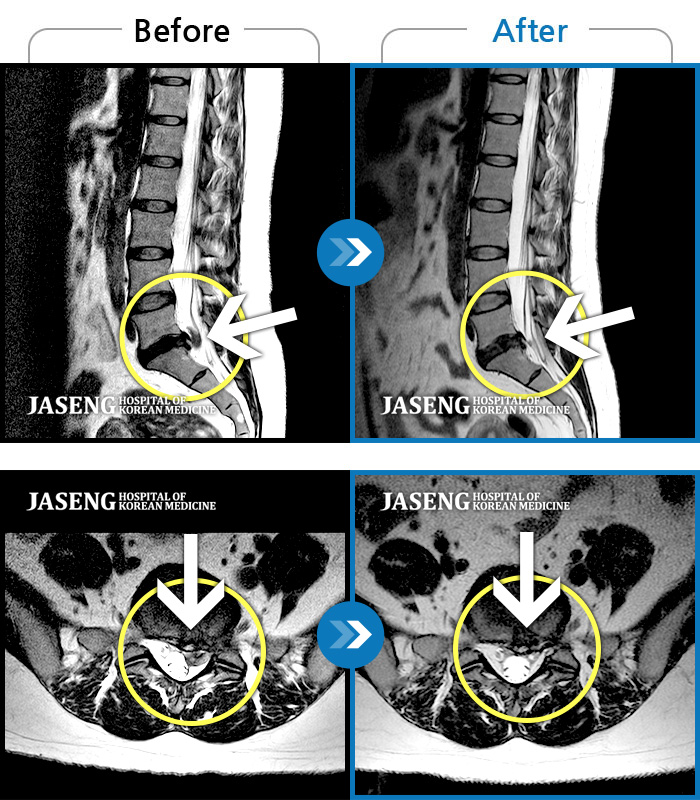

MRI 치료사례

통증으로 아기를 안지 못하던 여자분입니다